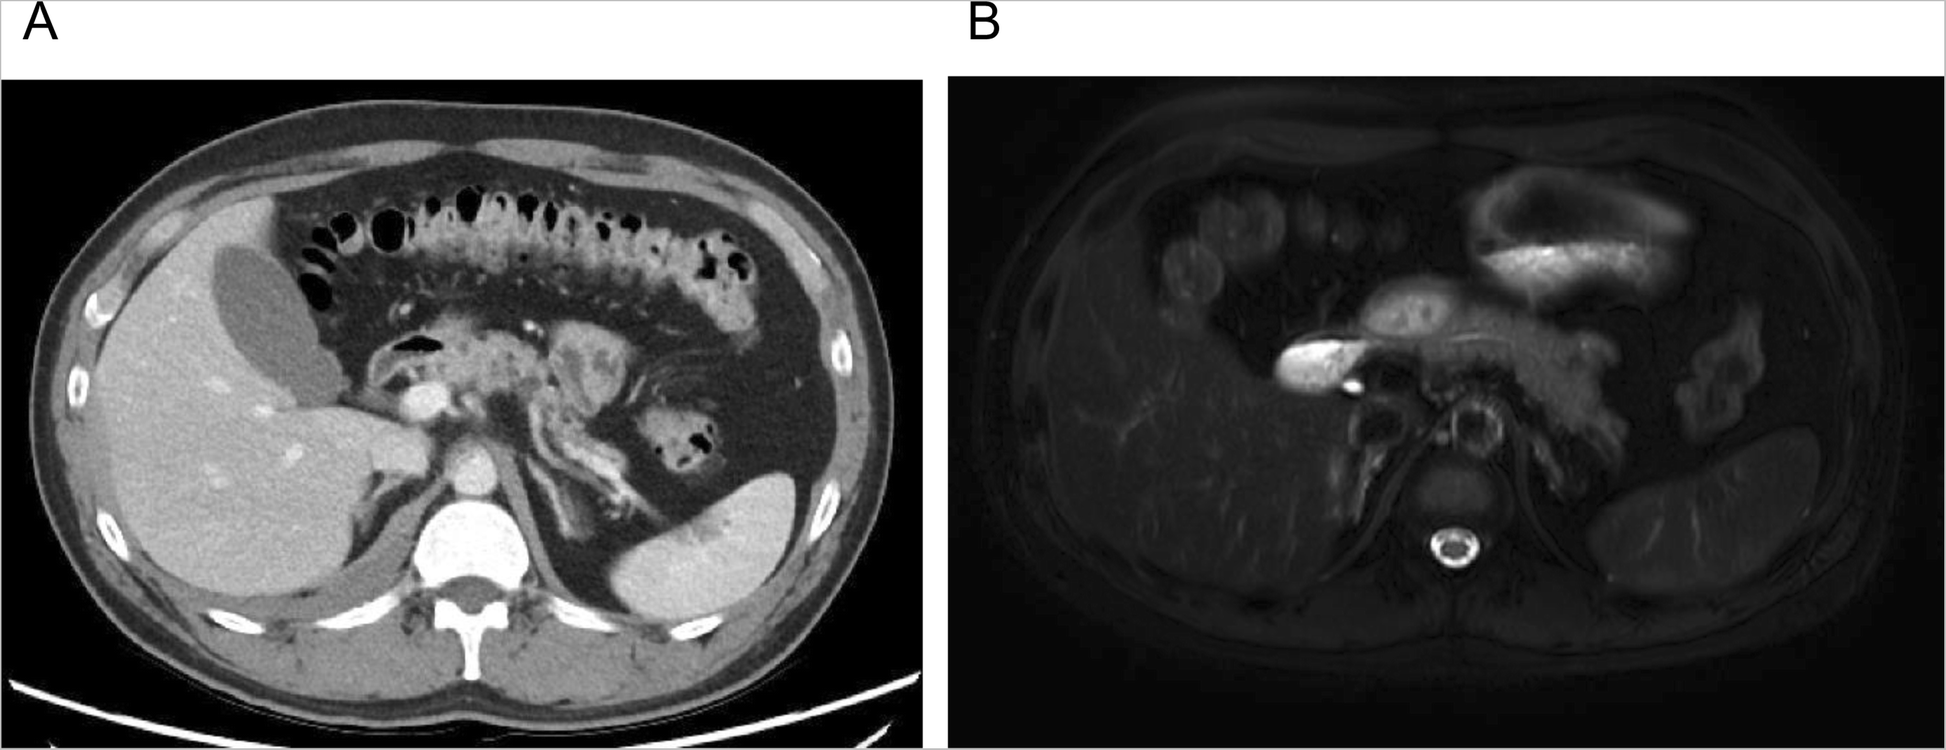

Fig. 3From: A rare case of multiple endocrine neoplasia type 1 initially presenting as an asymptomatic, huge mediastinal mass: case reporta Abdominal CT showing multiple small hypodense lesions in the head and body of the pancreas. b Magnetic resonance imaging demonstrates a normal pancreasBack to article page